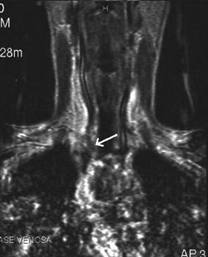

Femeie de 36 ani. Cunoscuta cu maladie Graves. La un

an dupa prima tiroidectomie totala pentru neoplazie papilara multifocala cu

metastaze in ganglioni (pT4b N1 M0).

Mica formatiune nodulara medial de carotida dreapta (0,2 cc), marcat

hipoecogena.

Tireoglobulina: < 2 ng.

Examen citologic: carcinom papilar.

Aceeasi pacienta - hipervascularizatie interna la doppler color si powerdoppler

Aceeasi pacienta cu mica formatiune

nodulara medial de carotida dreapta - IRM